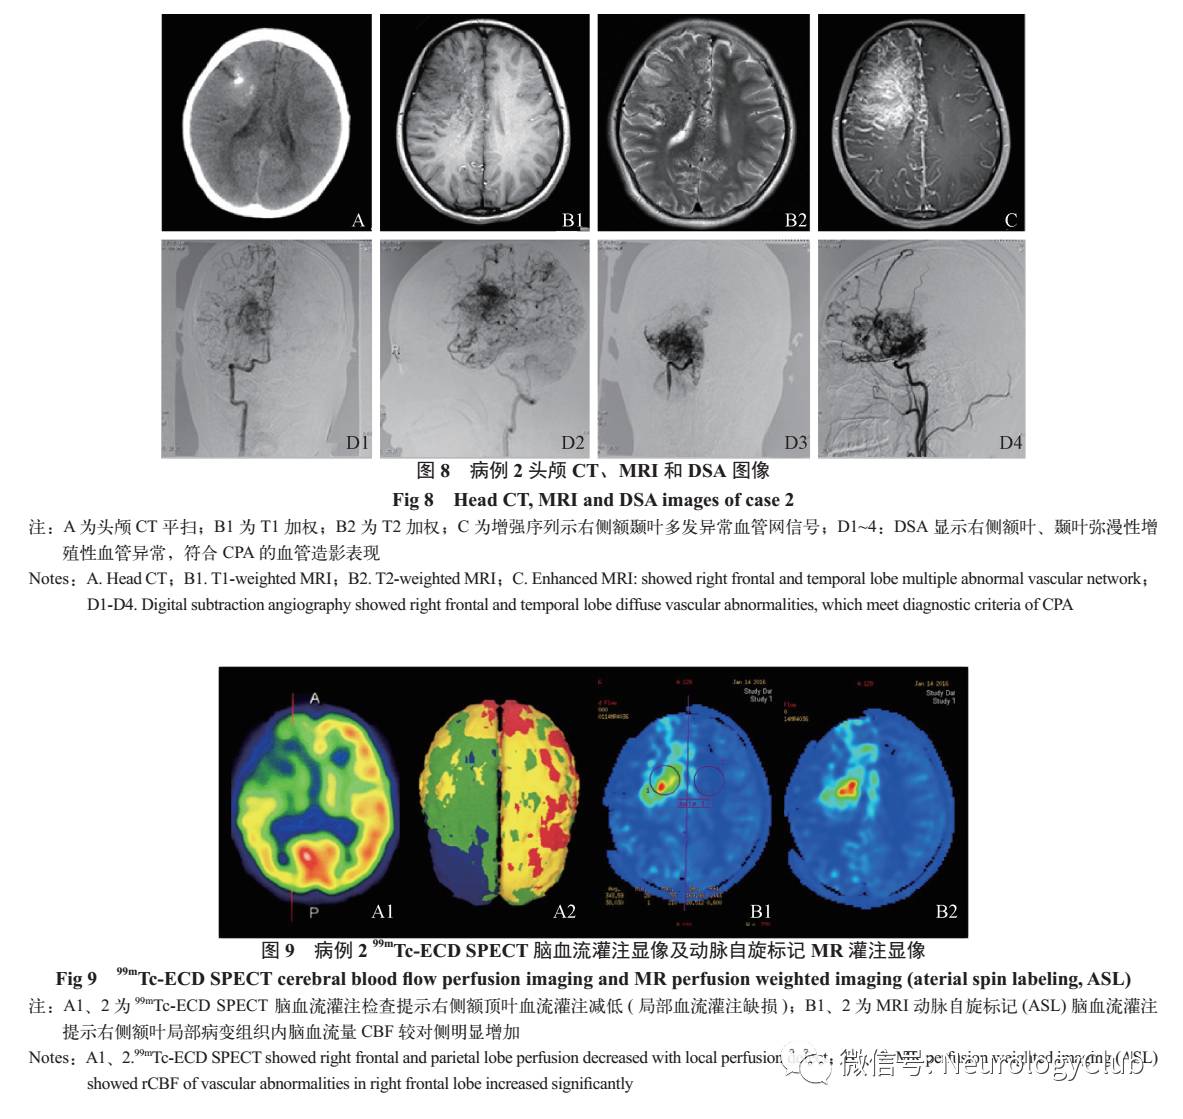

4. 影像学检查:①头颅CT平扫、头颅MRI平扫+增强显示右侧额颞叶弥漫分布异常血管网(图8);②全脑血管造影术显示右侧额叶、颞叶弥漫性增殖性血管异常,符合CPA的血管造影表现(图8);③99mTc-ECD SPECT脑血流灌注检查提示右侧额叶血流灌注减低(局部血流灌注缺损),见图9;④头颅MR灌注(动脉自旋标记/ASL)提示右侧额叶局部病变组织内CBF较对侧明显增加(图9)。